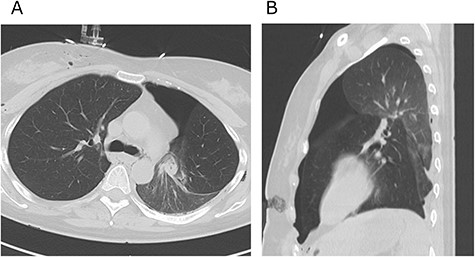

A 38-year-old woman with schizophrenia committed suicide by a self-infliction of sharp force into the chest and abdomen. She presented to our hospital in a critical condition. On arrival in the emergency room (ER), she developed hemorrhagic shock, which leads to an emergent abdominal damage control surgery under general anesthesia. She lost cardiac activity in the operating room during exploratory laparotomy. A left-sided basal thoracostomy, cross-clamping of the descending thoracic aorta, and open cardiac massage were also performed. She received gauze packing at the bleeding point and temporarily close the abdomen and chest wall. After the surgery, she was transferred to the intensive care unit with mechanical ventilation and recovered from hemorrhagic shock. Two days later, a second-look laparotomy was performed. ER doctors verified the hemostasis and closed the patient’s abdomen and chest. On the same day, a chest radiograph revealed pulmonary atelectasis of the left upper lobe (Fig. 1). Computed tomography (CT) revealed alveolar bleeding, pneumonia and atelectasis of the left upper lobe (Fig. 2). Despite antibiotic therapy and repeated endobronchial sputum aspiration, radiologic findings were not improved. On the seventh postoperative day, she was referred to our department for suspected lung abscess. When compared to the chest CT images on the day of initial surgery, pulmonary torsion was suggested (Fig. 3A). The sagittal CT images were reconstructed, and the torsion of the left upper lung lobe was diagnosed (Fig. 3B). Therefore, an emergency left upper lobectomy was performed through a left thoracotomy. Intraoperatively, the left upper lung lobe was rotated clockwise and was hemorrhagically and congestive infarcted. Due to severe pulmonary congestion, it was difficult to obtain the surgical field of view. The pericardial sac was opened and the intrapericardial isolation of the left upper pulmonary vein was performed. To prevent separation of the thrombus and necrotic material in the left upper lobe, we first dissected the left upper pulmonary vein before resolving the torsion and performing the lobectomy. She had a complete pulmonary fissure. Moreover, only one first pulmonary artery branch had ruled the approximately pulmonary arterial flow of her left upper lobe. The left upper lobectomy was performed. The patient made an uneventful recovery.

Computed tomography images of 2 days after initial emergency operation.

Axial (A) and sagittal (B) computed tomography images few hours after initial emergency operation.